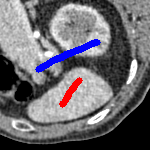

We now introduce two recent methods that incorporate user input to perform selective segmentation. Each involves input in the form of foreground/background regions to indicate relevant structures of interest. An example of this can be seen in Fig. 18, where red regions indicate foreground and blue regions indicate background. We compare against the work of Nguyen et al. Nguyen:12 , which uses a similar convex relaxation framework to the proposed approach, and Dong et al. SRW , which uses a variation of the random walk approach. We summarise the essential aspects of each approach in the following.

Test Images. We will perform initial tests on the images shown in Figs. 5–7. We have provided the ground truth and initialisation used for each image. Test Images 1–3 are synthetic, Test Image 4 is an MRI scan of a knee, Test Images 5–6 are abdominal CT scans, and Test Images 7–9 are lung CT scans. They have been selected to present challenges relevant to the discussion in §2. We focus on medical images as this is the application of most interest to our work. In the following we will discuss the results in terms of synthetic images (1–3) and real images (4–9). We also test the proposed approach on a larger data set of 30 CT images (a sample of which is presented in Fig. 18), comparing against existing selective methods detailed in §3.

In order to further establish the robustness of our method, we now introduce the results of testing our approach against competing interactive segmentation methods on a larger data set. The results are presented in Fig. 17, showing a boxplot of accuracy in terms of TC on a set of 30 CT images (excluding outliers). The target structure we consider is the spleen, as this consists of a relatively homogeneous foreground, appropriate for the approach considered. The data has been manually contoured providing ground truth data for the image set. We compare CAC Nguyen:12 and SRW SRW against our method with five variations of user input for each image. It is worth emphasising here that the input used in the tests is identical for each approach and was not refined in any way. It was designed to mimic what a user, unfamiliar with each approach, might select intuitively. A representative example for three images is shown in Fig. 18. This shows foreground (red) and background (blue) user input regions. For our method, we define the red region as as discussed in §1 and enforce hard constraints on the blue region. We refer to the results of the proposed approach using this input as Ours (i). We also include results of randomising the user input in an identical way to §7.3. For each image we generate 1000 simulated user input choices, which we present as Ours (ii). It is important to note that the difference between Ours (i) and (ii) is only the definition of . The method and parameters are fixed between each.